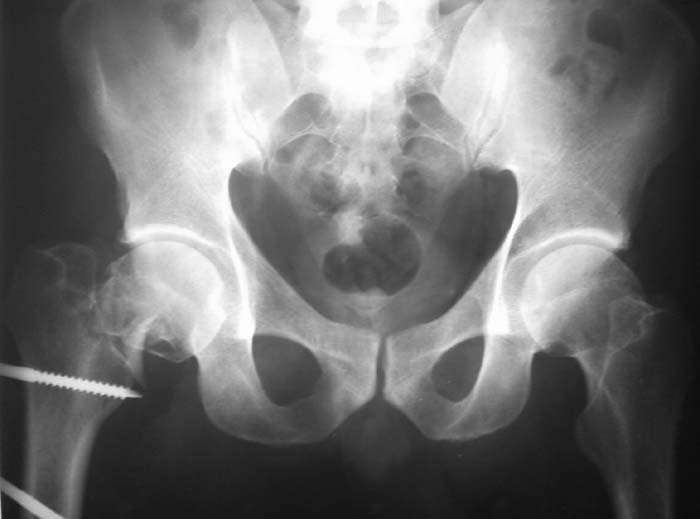

Мужчина, 44 г. Травма в ДТП 22.08.08: открытый перелом ср\3 диафиза правой бедренной кости, закрытый оскольчатый перелом правого локтевого отростка со смещением, в\3 правой лучевой кости со смещением, закрытый перелом верхушки внутренней лодыжки правой голени.

Находился на лечении в одной из городских больниц (где в ургентном порядке произведена операция - ПХО ран, ЧКО правого бедра аппаратом спице-стержневого типа, иммобилизация правого предплечья гипсовой повязкой). Переведен для дальнейшего лечения в ДНИИТО. Через 18 дней после травмы выполнены рентгенограммы таза - диагностирован перелом шейки бедра. На данный момент раны бедра заживают вторично с участками некроза.

Male, 44 y.o. Trauma in MVA 22.08.08: open fracture of right femur (middle shaft), close fractures of right elbow and pilon.

He was in rural hospital were debridgement and Ilizarov frame for femur were performed. Now, he is in Regional Trauma Hospital. After 18 days of trauma x-ray of pelvis were performed – fracture of right femur neck. Wounds at femur is healing with small points of necrosis.